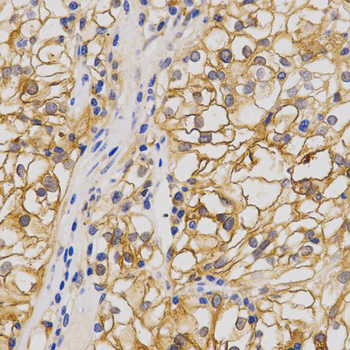

• A1826: image 2

Immunohistochemistry of paraffin-embedded human stomach cancer using GRIA1 antibody at dilution of 1:200 (x400 lens)